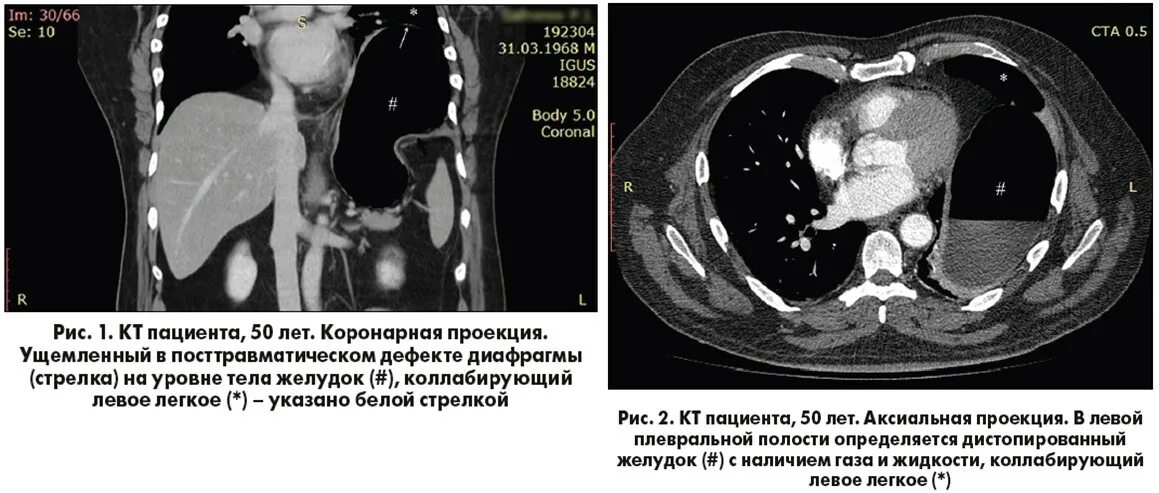

Ущемление грыжи диафрагмы